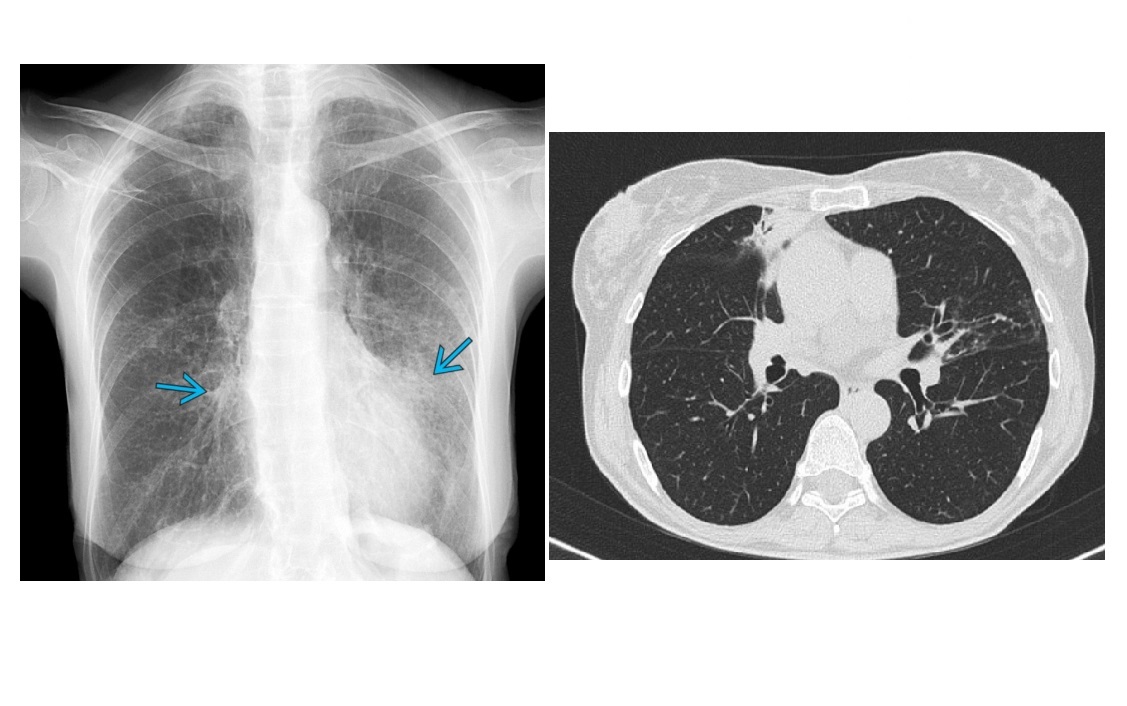

ABPA

‘Migratory’ airway consolidation

**Central (saccular) and upper lobe predomiannt bronchiectasis

(peripheral bronchi clasically spared)

**Dense mucoid impaction/finger in gloove - High-attenuating (>70–100 HU) bronchial contents represent fungal debris

Asthma

Cavity formation possible in later stage